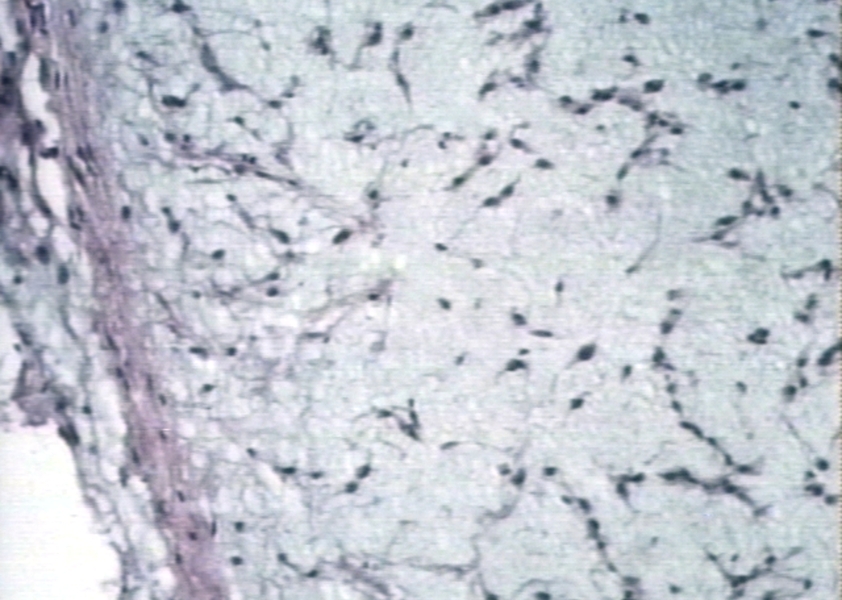

HISTOLOGY: BONE: CHONDROSARCOMA; Neoplasm.

bone, histology